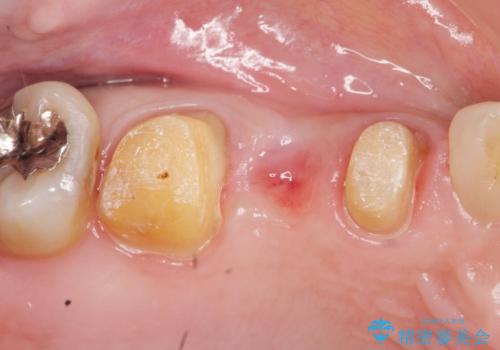

虫歯による歯の崩壊で歯を残すことが難しかったので抜歯を行い、インプラント・入れ歯ではなくブリッジによる咬合機能の回復を希望されました。

- 33万円(仮歯・ジルコニアクラウン×3)費用は治療当時の料金となります

ブリッジは隣の歯を削り、クラウンにしなければならないというデメリットはありますがインプラントと異なり手術をしなくてもよく、入れ歯よりも一般的にしっかりと噛むことができます。